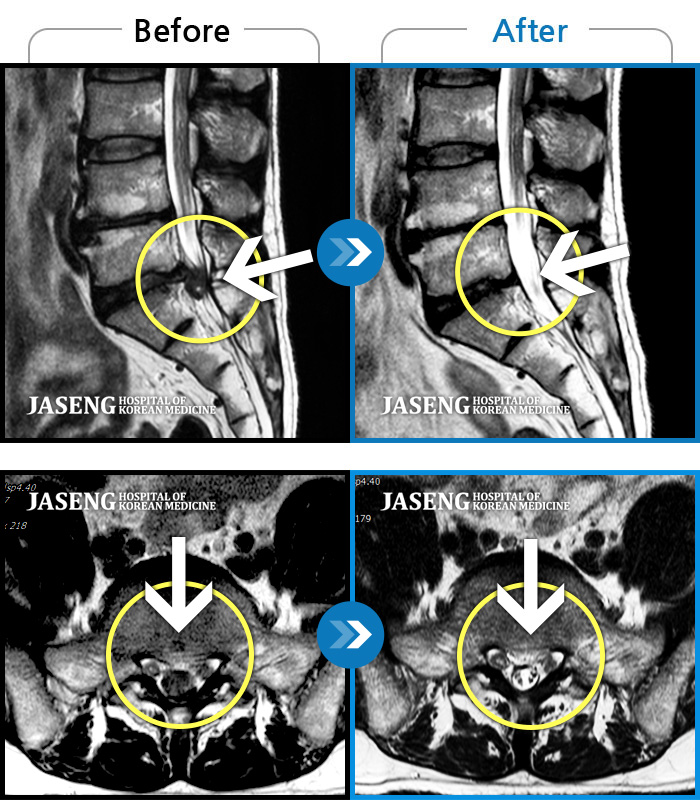

목디스크

강남 · 강만호 원장

양측 승모근 통증과 목 통증, 견갑골 통증으로 고개를 돌릴때 통증을 호소하는 환자였습니다.

촬영시기

2019.11.18 ~ 2024.07.30

2024.08.09